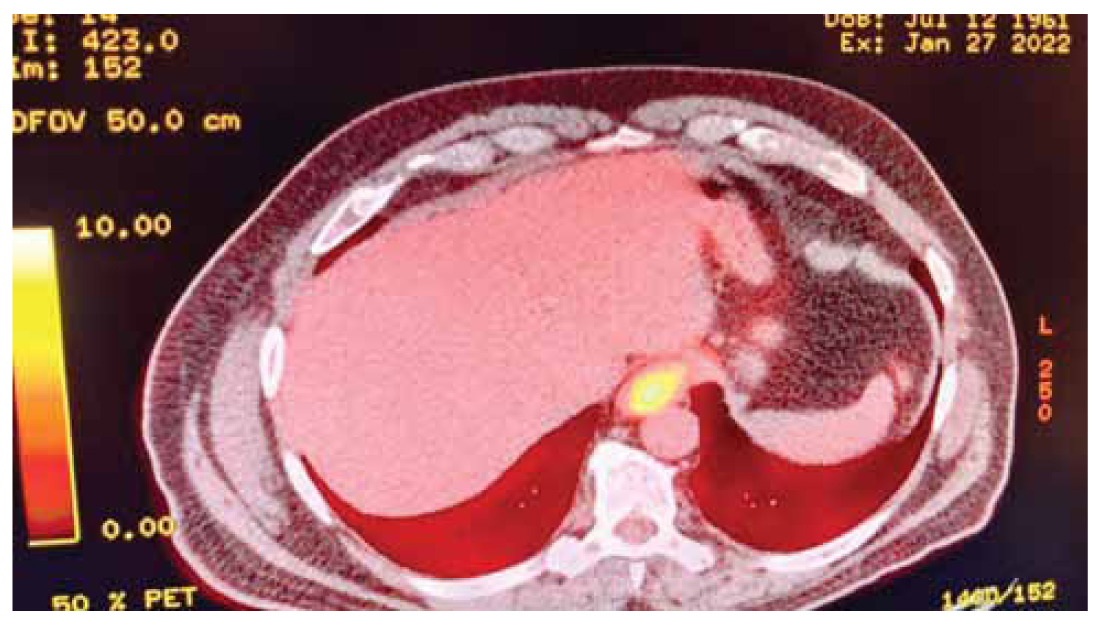

A 61-year-old male patient presented to the hospital reporting three-month worsening dysphagiato solid food, and unintentional weight loss of 6 kilograms within two months. Biochemical examination showed mild anaemia- haematocrit (37%), hemoglobin (11,8 g/dl), MCV (70,9 fL), MCH (22,6 pg/cell) and elevated CRP (96,3 mg/L). Tumour markers CEA and CA19-9 were found to be mildly elevated (22,3 ng/ml and 59,1 IU/ml respectively). The patient’s personal history included arterial hypertension and an angioplasty that had taken place 15 years prior. Firstly, a CT scan reported a mass at the level of the gastroesophageal junction. A PET/CT scan was then performed which revealed a lesion on the cardioesophageal junction with high 18F-FDG uptake (cT3N0M0) (Figure 1).

Figure 1. PET/CT scan that was performed when the patient was firstly diagnosed with the disease. A lesion with high absorption of 18F-FDG and thus elevated SUVmax can be observed in the gastroesophageal junction.